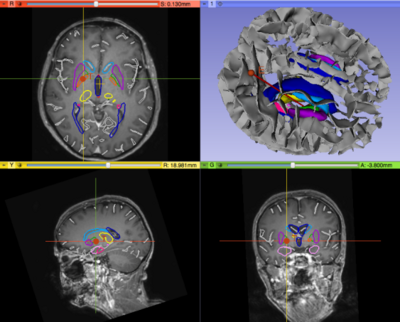

Pydbs.png

Project Description

Objective

• Upgrade of the PyDBS modules for Parkinson Surgery to Slicer4.4

Approach, Plan

• Upgrade to new Markups module

Progress

• Upgrade Slicer plugins from 4.3 to 4.4

• VTK5 to VTK6

• Fiducial to Markups

• Listeners to mouse events on slice view

• Electrophysiological workstation connection